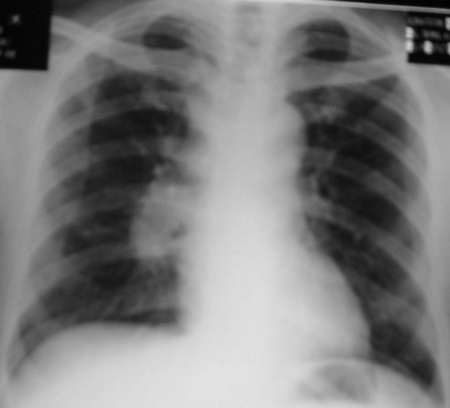

男,42岁。半年前体检发现右侧肺门肿大,mri示右侧肺门淋巴结肿大。腰背部疼痛伴右腿麻木1月入院。腹部b超示肝、胆、胰腺、脾、肾、前列腺及膀胱未见异常。afp、cea、ca199均正常。

胸部mri是半年前的,而胸部 增强ct是目前的,二者变化不大,肺部好像也没啥。

增强图像显示不清,好像有肺门及纵隔与腋下淋巴结肿大,右侧胸腔积液,腰1椎体骨质破坏,椎旁软组织肿块形成,其后硬脊膜囊明显受压。考虑淋巴瘤可能。其他待排。